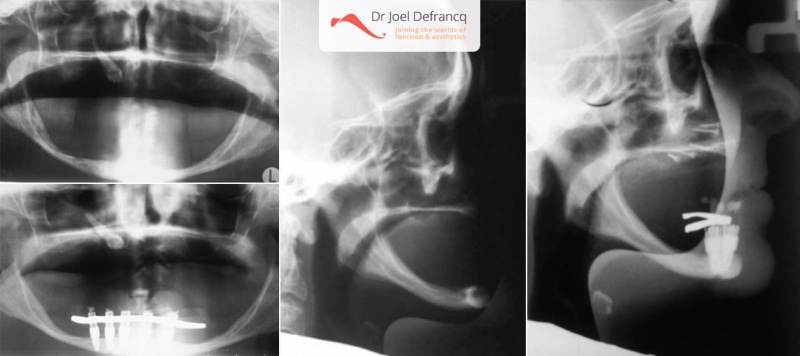

Dr. Defrancq plaatst regelmatig implantaten met rechtstreekse loading in onderkaken die zelfs extreem weggekwijnd zijn (7 tot 10 mm hoogte!). Het is uiterst zeldzaam dat een onderkaak nood heeft aan botopbouw. Bij dergelijke ingrepen wordt bovendien de gevoelszenuw vaak geschonden met verlies van gevoel in de onderlip. Bovendien is een botopbouw in de onderkaak zeer gevoelig voor terug weg te kwijnen en te verdwijnen, waardoor de implantaten later te hoog uitsteken. Deze casus van de onderkaak illustreert dat we zelfs in de uiterst geresorbeerde gevallen nog implantaten plaatsen. Tijdens de planning is het van belang om grotere afstanden tussen de implantaten te respecteren en aldus kaakfracturen te vermijden. Vandaar ook het belang van de rechtstreekse loading met een vaste structuur, omdat deze dan fungeert als een spalk.

Een patiënt met de ziekte van Parkinson door Dr Defrancq aldus behandeld. De implantaten werden geplaatst onder lokale verdoving en de tanden werden er enkele dagen later vast opgeschroefd .